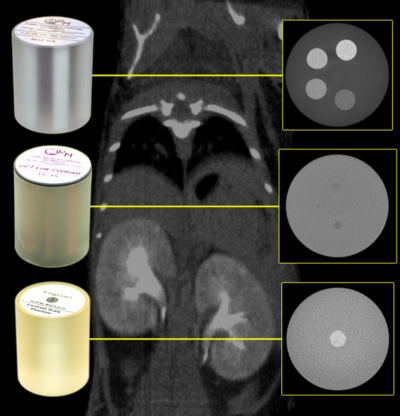

QRM-Cardio-Thorax, Liver and Low-Contrast Insert. Phantoms for measuring coronary artery calzifications, liver lesions and low contrast capability of CT scan protocols.